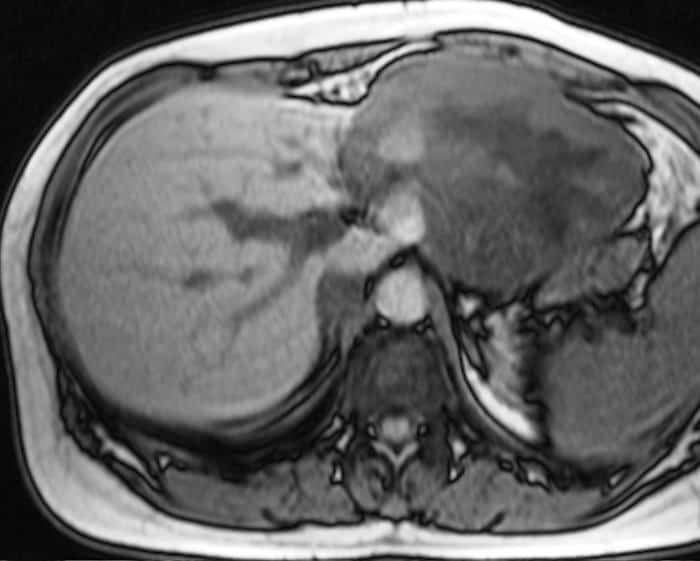

U máu gan

» Thông tin: Nữ giới – 47 tuổi.

» Lâm sàng: Đau thượng vị.